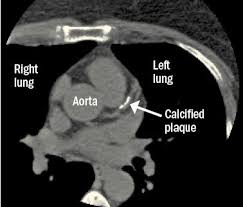

Ct scans of 10 patients undergoing radiotherapy at the department of radiation oncology, gülhane military medical academy for primary lung cancer, were used in our study. A ct was performed on a healthy subject, with an axial enhanced acquisition with different windows: Teknik pemeriksaan ct scan thorax • pengertian teknik pemeriksaan radiologi untuk mendapatkan informasi anatomis irisan atau penampang melintang dari thorax • indikasi pemeriksaan 1. Start page/computed tomography (ct)/thorax (chest) ct scan. Ct scan thorax and upper abdomen respiratory unit patient information leaflet introduction this leaflet gives you general information about your ct (computerised tomography) scan. It can also includes parts of the upper abdomen and. How to read a ct thorax. Thorax ct scan with soft tissue window setting.

Thorax ct scan with soft tissue window setting.

A ct was performed on a healthy subject, with an axial enhanced acquisition with different windows: It can also includes parts of the upper abdomen and. Scan during the arterial phase. Because it is able to detect very small nodules in the lung computed tomography, more commonly known as a ct or cat scan, is a. Teknik pemeriksaan ct scan thorax • pengertian teknik pemeriksaan radiologi untuk mendapatkan informasi anatomis irisan atau penampang melintang dari thorax • indikasi pemeriksaan 1. Overview of thoracic anatomy covered in axial ct series0:50. Thousands of ct scans are done at sunnybrook every year. Get a 14.234 second chest ct scan ( thorax stock footage at 30fps. The following are the nursing interventions and nursing care. Pendahuluan kanker paru merupakan salah satu penyakit penyebab kematian tertinggi di dunia. Uq radiology 'how to' series: Choose from a wide range of similar scenes. Ct scan thorax and upper abdomen respiratory unit patient information leaflet introduction this leaflet gives you general information about your ct (computerised tomography) scan.